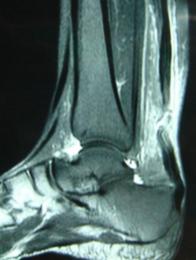

跟腱断裂的核磁共振图像

跟腱断裂回缩4、跟腱断裂的诊断

跟腱断裂的诊断主要依据患者的病史、体格检查(腓肠肌试验),以及超声检查和MRI检查,可以清晰显示断裂部位。